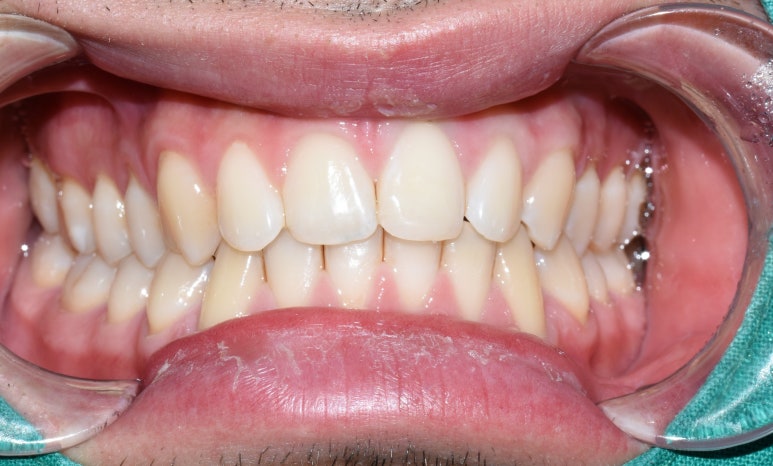

(파절된 부위가 큰 경우 크라운을 하는 것이 더 안정적인 예후일 수 있으며

해외 환자의 경우 임시로 레진을 진행하기도 하였습니다.)

파절 앞니 레진 전후

앞니 벌어진 부위는 부분교정, 무삭제 부분라미네이트, 무삭제 라미네이트, 레진 등

그 공간을 메우는 여러 방법이 있지만

케이스에 맞는 방법을 고르는 것이 중요하므로 원장님과 상담이 필요합니다!